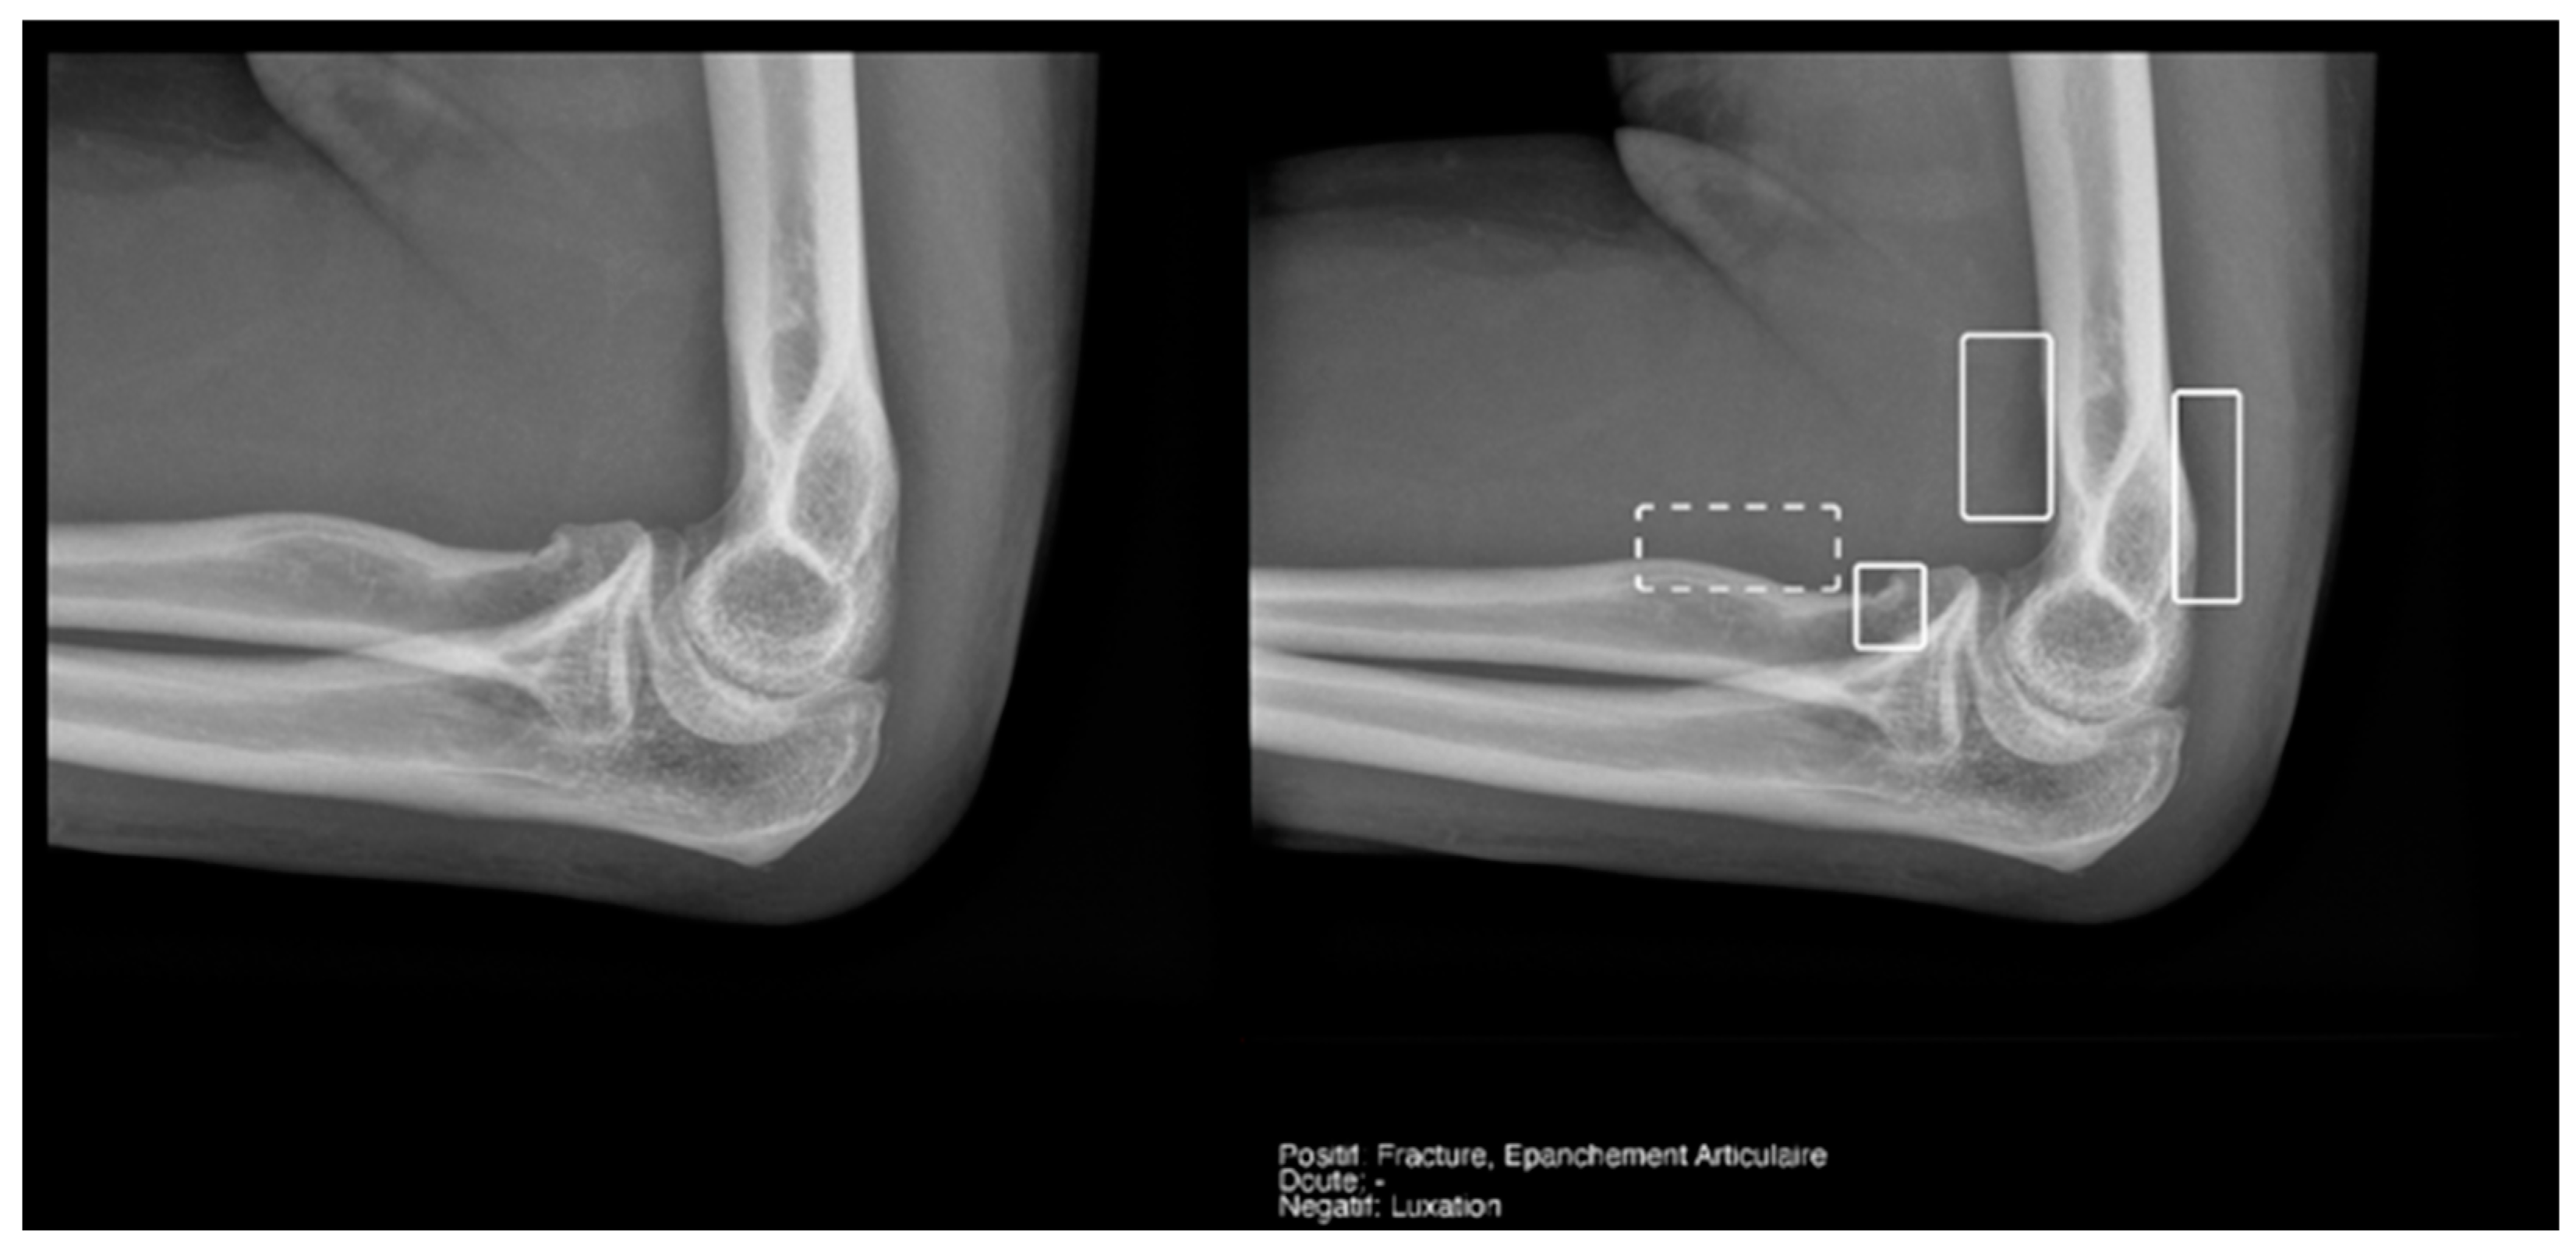

3.3.3. Elbow Joint Effusion